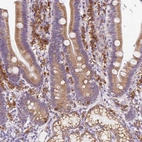

Immunohistochemical staining of human duodenum shows cytoplasmic positivity in leukocytes and glandular cells.